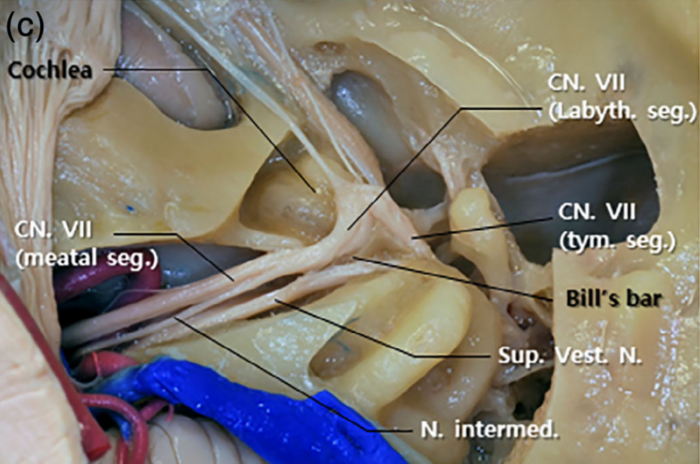

- Jak układają się włókna nerwowe w przewodzie słuchowym wewnętrznym

- Podział nerwu twarzowego na segmenty ze szczegółowym opisem ich topografii (przy okazji sporo będzie informacji na temat budowy ucha)

- Jakie gałęzie odchodzą lub dochodzą do nerwu twarzowego w poszczególnych segmentach

- Jak układają się włókna nerwowe w przewodzie słuchowym wewnętrznym

- Podział nerwu twarzowego na segmenty ze szczegółowym opisem ich topografii (przy okazji sporo będzie informacji na temat budowy ucha)

- Jakie gałęzie odchodzą lub dochodzą do nerwu twarzowego w poszczególnych segmentach